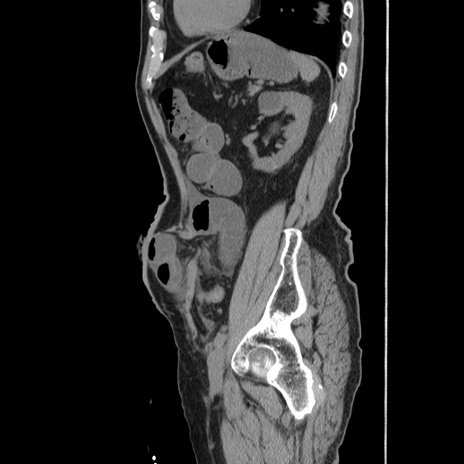

症例24(矢状断像)

【症例】80歳代男性

【主訴】左側腹部痛、嘔吐

【現病歴】本日早朝より左腹部に痛みあり。昼頃嘔吐認めたため、救急要請。

【既往歴】直腸癌(Mile手術)、胆摘

【身体所見】意識清明、BT 35.9℃、BP 221/93mmHg、SpO2 97%(RA) 、腹部:左ストーマ周囲に限局性の腹部膨隆あり。 膨隆部自発痛・圧痛あり・軟。

【データ】WBC 7700、CRP 0.09